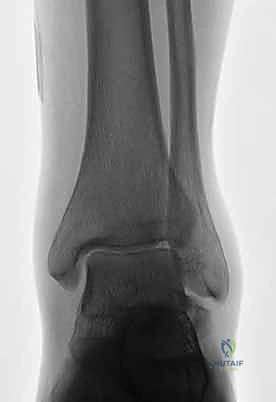

2. التصوير الإشعاعي (الأشعة السينية - X-rays)

هي الخطوة الأولى. تُطلب صور من زوايا متعددة:

* الرؤية الأمامية الخلفية (AP).

* الرؤية الجانبية (Lateral).

* رؤية الهاون (Mortise view).

المرحلة الخامسة: التحقق الإشعاعي الفوري والإغلاق

قبل إنهاء العملية، يستخدم الدكتور هطيف جهاز الأشعة السينية المتحرك داخل غرفة العمليات (C-arm Fluoroscopy) لأخذ صور متعددة والتأكد من:

1. المحاذاة المثالية للكسر.

2. عدم وجود أي فجوات أو درجات في السطح المفصلي.

3. الطول والموقع الصحيح للمسامير (للتأكد من أنها لا تخترق المفاصل المجاورة).